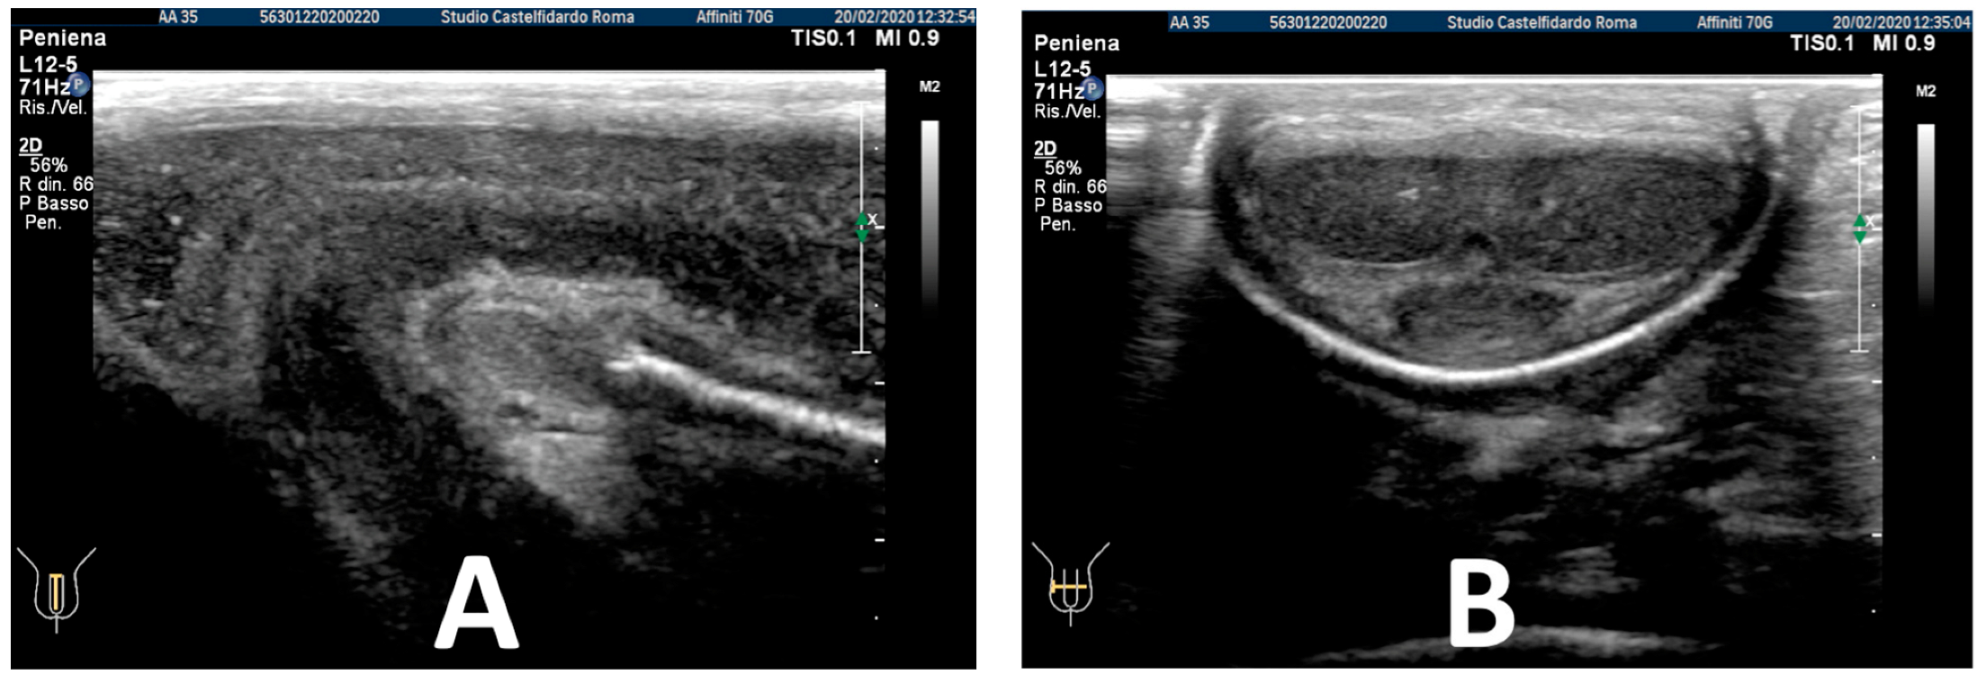

| 2 | 32 years | lichen sclerosus, chronic prostatitis | Proximal third | (A) 16.4 × 8.27 × 3.09 mm volume = 219 mm3 | (A) 10-degree left curvature | (A) score 3 | (A) score 26 | 2 years and 9 months | orally: Silymarin 400 mg + Ginkgo biloba 250 mg + Propolis 600 mg + Bilberry 160 mg + Vitamin E 800 IU/once a day, for 33 months. + topically: Propolis creme/twice a day/for 33 months. + peri-plaque penile injections: Pentoxifylline 100 mg (30 G needle) every 15 days for 6 months, and then monthly for 12 months, and then 1 injection every other month. for 12 months (total = 30 injections) |

| (B) No plaque detected | (B) None | (B) score 0 (after six months) | (B) score 28 | ||||||